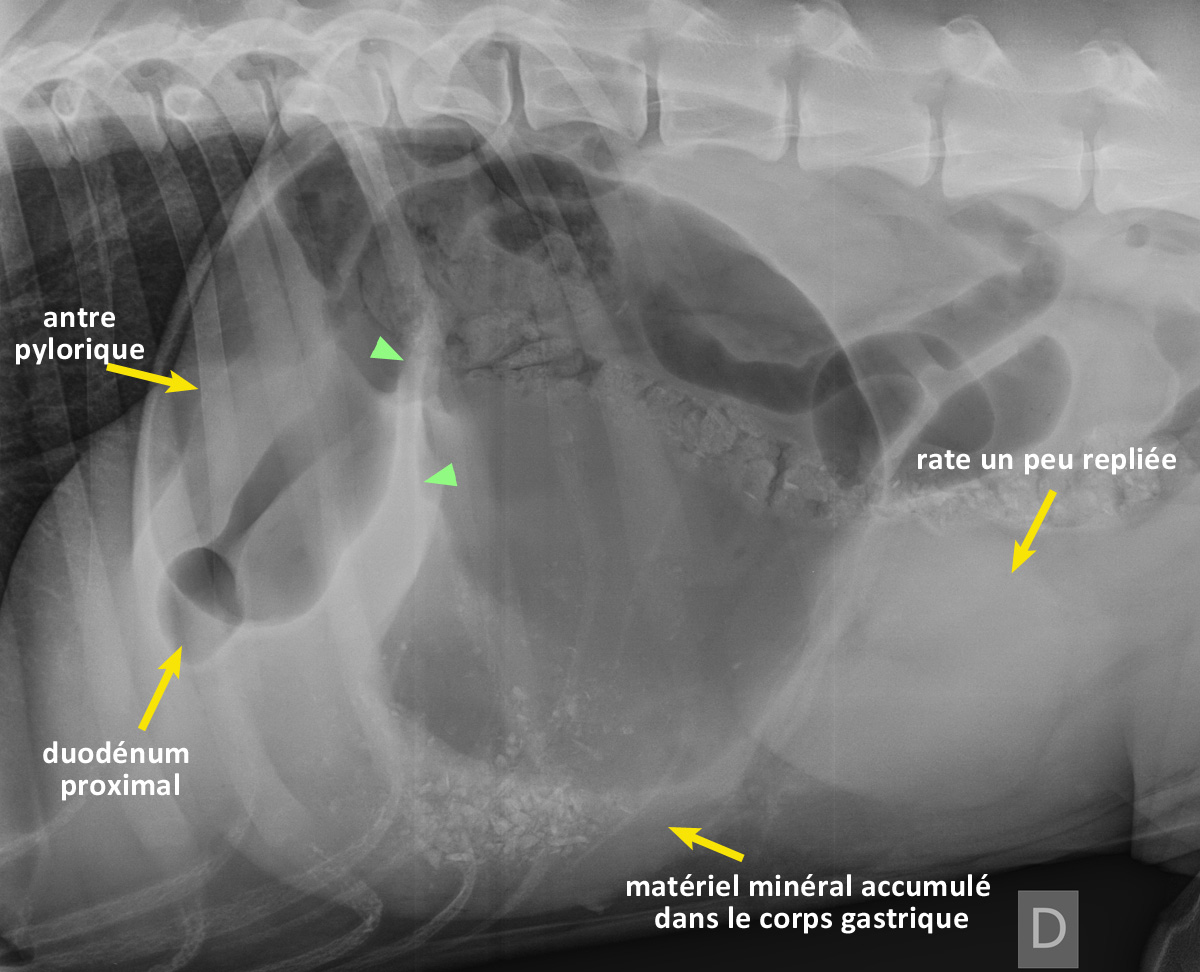

RadioQuiz 2: Tordu ou pas cet estomac ? Réponse

Eh oui… il est tordu cet estomac. Remarquez la position de l’antre pylorique, qui se retrouve crâniodorsalement, séparée du corps gastrique par une bande de tissu (têtes de flèches vertes) créant deux compartiments. La rate est poussée caudalement et semble arrondie, possiblement en raison d’une congestion veineuse, ou parce qu’elle est repliée partiellement sur elle-même.

(cliquez sur l’image pour la voir en plein écran)